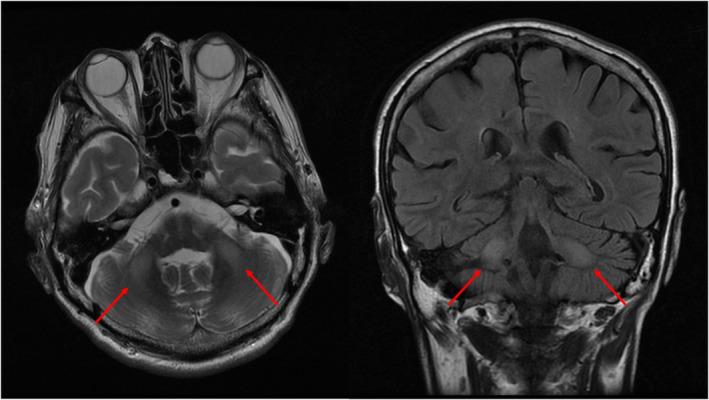

A 61-year-old man was transferred to our hospital following a suicide attempt. The patient lost consciousness after an overdose of disulfiram and brotizolam. He was diagnosed with acute drug intoxication and was intubated. On day 2, he showed an improved consciousness response and was successfully extubated. On day 5, the state of consciousness worsened again, and ketoacidosis progressed. The patient required hemodialysis and suffered from impaired consciousness for the following 2 weeks. Eventually, he recovered gradually and was discharged to the rehabilitation ward.

一名61岁男性在自杀未遂后被转至我院。该患者在过量服用双硫仑和溴替唑仑后失去意识。他被诊断为急性药物中毒并接受了插管。第2天,他的意识反应有所改善并成功拔管。第5天,意识状态再次恶化,酮症酸中毒进展。患者需要进行血液透析,并在接下来的2周内一直存在意识障碍。最终,他逐渐康复并被转至康复病房。